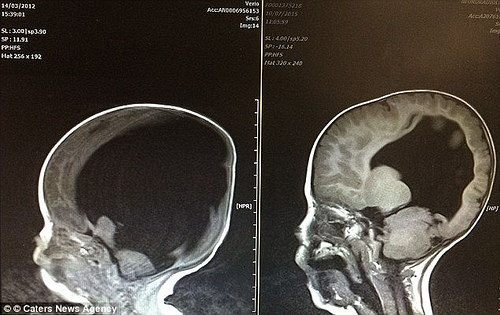

一如预期,由于脑水肿的液体损害结果,Noah一出生就有98%的大脑没有功能。但接下来发生的事情是一个奇迹。

尽管情况似乎是不可逆转的,但是Noah的头脑开始逐渐地长回来。

Noah拒绝放弃,而且现在向所有的医疗成功机率挑战。他的大脑扫描现在被医学研究人员用来帮助增加对脊柱裂的理解。